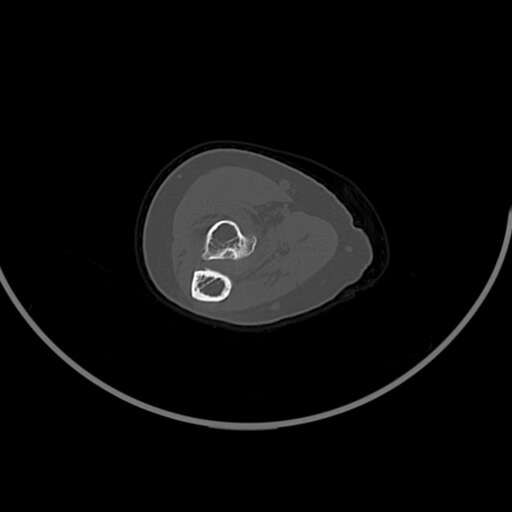

左肘部肿物

图1

女83岁,